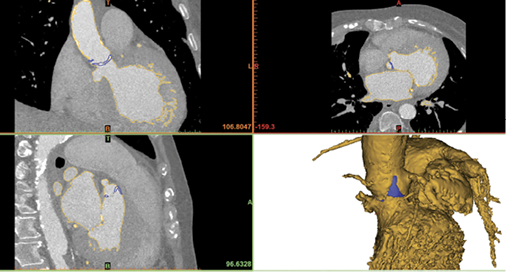

Dr. Chepelev, a member of RSNA’s 3D Printing Special Interest Group, is exploring how AI can improve the burgeoning technology of 3D modeling. The segmentation process used in building a model can take hours and is limited by the quality of the image. AI can significantly speed up this process while improving the image quality, which is an important consideration for surgeons who might be planning, for example, to remove a tumor that is near vital structures like blood vessels. “I think all these tools will ultimately improve the accessibility of the pathology depicted by radiology and will help us to communicate with surgeons and the patient as well,” Dr. Chepelev said.